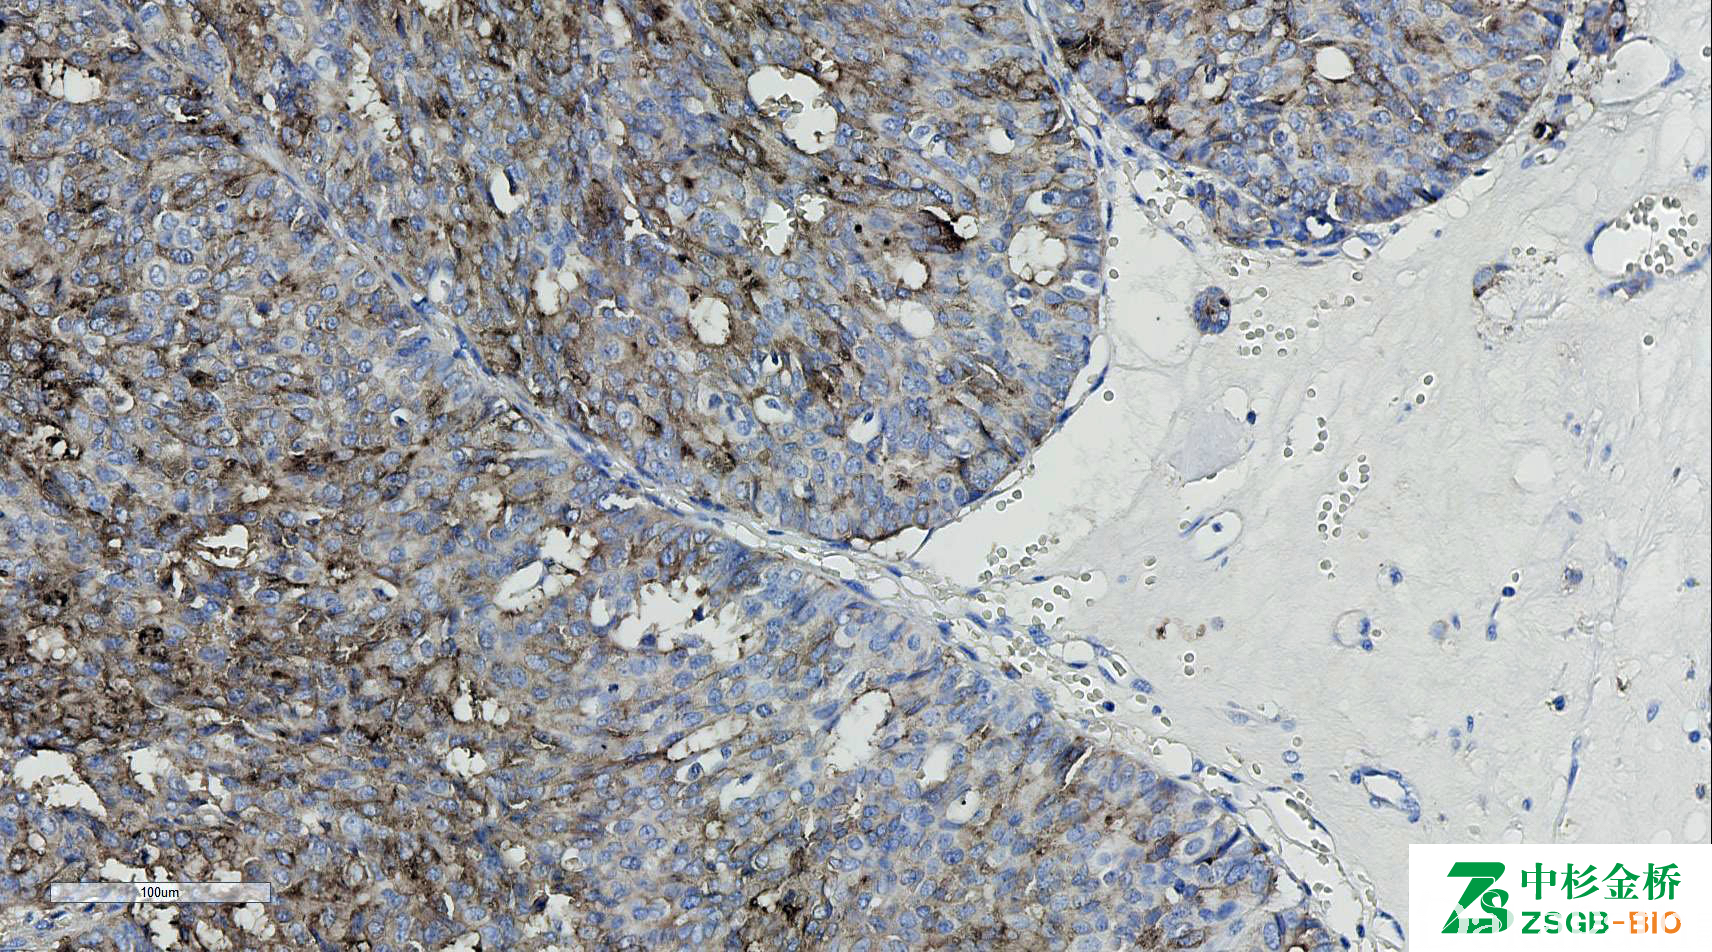

Mammaglobin

分泌蛋白家族成员,乳腺相关糖蛋白,由乳腺组织分泌,对乳腺癌组织中的乳腺球蛋白高度敏感(80%)。

信号定位: 胞质

与 GCDFP15 联合应用用于乳腺癌的鉴别论断。